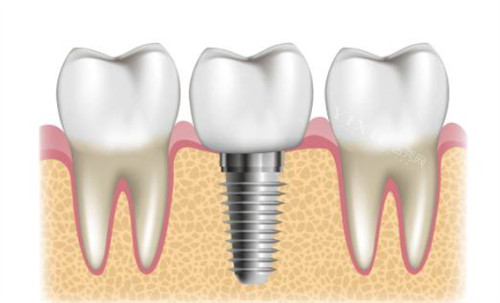

拜阿蒙种植体采用4级纯钛材质,这与多数进口品牌使用的材料等级相同。纯钛具有优异的生物相容性,能够比较好地与人体组织融合,同时具备很强的耐腐蚀性能,确保长期使用的可靠性。在表面处理工艺方面,拜阿蒙引进了韩国SLA喷砂技术,这种处理方式能显著提升种植体表面的亲水性。亲水性增强后,种植体与骨组织的结合速度会更快,这对缩短治疗周期很有帮助。

拜阿蒙种植体在结构设计上有两个突出特点。首先是颈部双螺纹设计,这种结构使植入过程更加顺畅,医生操作更方便,同时植入后的稳定性也更强,特别适合即刻种植的情况。其次是应用了多孔纳米氧化钛技术,这项技术能有效增强种植体的生物活性,降低人体对异物的排异反应,为骨结合创造更有利的条件。这些设计细节的优化,对提升整体性能起到了关键作用。

从实际使用结果来看,拜阿蒙种植体表现出三个明显优势。稳定性方面,其多重微螺纹设计显著增加了与颌骨的接触面积,植入后固位力更强,不易松动。安心性方面,钛金属本身对神经组织无刺激性,能够有效保护牙槽骨结构,避免骨质吸收和萎缩的问题。使用寿命方面,在正确维护的情况下,这款种植体可使用长达40年之久,远超过传统假牙的使用年限。这些临床特点使其成为可靠的长期修复方案。